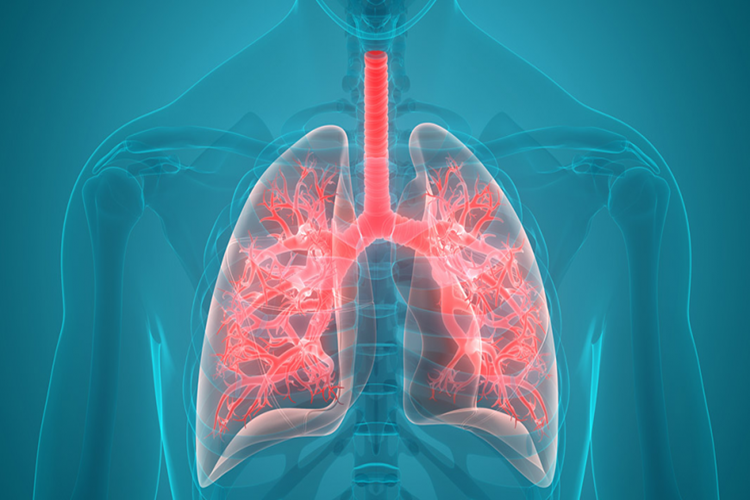

Zatürrenin Tedavisi Var Mı?

Zatürre tedavisi aşağıdaki unsurları içerebilir:

Antibiyotikler: Bakteriyel zatürre tedavisinde antibiyotikler sıklıkla kullanılır. Doktorunuz, enfeksiyonun türüne ve şiddetine bağlı olarak uygun antibiyotikleri reçete eder. Antibiyotikler genellikle semptomlar düzelene kadar birkaç gün veya birkaç hafta boyunca alınmalıdır. İlaçlar tam olarak doktorunuzun yönlendirdiği şekilde ve sürede kullanılmalıdır.

Antiviral İlaçlar: Viral zatürre (örneğin, influenza nedeniyle) durumunda, antiviral ilaçlar kullanılabilir. Bu ilaçlar virüslerin çoğalmasını engellemeye veya kontrol etmeye yardımcı olabilir.

Semptomatik Tedavi: Zatürre semptomlarını hafifletmek için ağrı kesiciler, ateş düşürücüler ve öksürük şurupları gibi semptomatik tedaviler kullanılabilir.

Rehidrasyon: İshal veya kusma gibi semptomlar nedeniyle dehidrasyon riski varsa, hastaya sıvı verilir.

Yatak Istirahati: Zatürre tedavisi sırasında dinlenmek ve yatak istirahati önemlidir. Bu, vücudun enfeksiyonla savaşmasına yardımcı olur.

Oksijen Tedavisi: Şiddetli zatürre vakalarında oksijen tedavisi gerekebilir. Bu, akciğerlerin yeterince oksijen almasını sağlamak için kullanılır.

Tedaviye erken başlamak, zatürrenin komplikasyonlarını ve yayılmasını önlemeye yardımcı olabilir. Ancak, zatürre tedavisinde en uygun yaklaşımı belirlemek için bir sağlık profesyonelinin gözetimine ihtiyaç vardır. Kendi kendinize antibiyotik veya diğer ilaçlar kullanmamalısınız.

Zatürrenin Tedavisi Var Mı?

Evet, zatürre (pneumonia) tedavi edilebilir bir enfeksiyon

hastalığıdır. Zatürre, akciğerlerin enfeksiyonu olarak tanımlanır ve bakteri,

virüs, mantar veya diğer mikroorganizmaların neden olduğu bir durumdur. Tedavi,

zatürrenin nedenini ve şiddetini belirleyen faktörlere bağlı olarak

değişebilir.

Zatürre tedavisi aşağıdaki unsurları içerebilir:

Antibiyotikler: Bakteriyel zatürre tedavisinde

antibiyotikler sıklıkla kullanılır. Doktorunuz, enfeksiyonun türüne ve

şiddetine bağlı olarak uygun antibiyotikleri reçete eder. Antibiyotikler

genellikle semptomlar düzelene kadar birkaç gün veya birkaç hafta boyunca

alınmalıdır. İlaçlar tam olarak doktorunuzun yönlendirdiği şekilde ve sürede

kullanılmalıdır.

Antiviral İlaçlar: Viral zatürre (örneğin, influenza

nedeniyle) durumunda, antiviral ilaçlar kullanılabilir. Bu ilaçlar virüslerin

çoğalmasını engellemeye veya kontrol etmeye yardımcı olabilir.

Semptomatik Tedavi: Zatürre semptomlarını hafifletmek için

ağrı kesiciler, ateş düşürücüler ve öksürük şurupları gibi semptomatik

tedaviler kullanılabilir.

Rehidrasyon: İshal veya kusma gibi semptomlar nedeniyle

dehidrasyon riski varsa, hastaya sıvı verilir.

Yatak Istirahati: Zatürre tedavisi sırasında dinlenmek ve

yatak istirahati önemlidir. Bu, vücudun enfeksiyonla savaşmasına yardımcı olur.

Oksijen Tedavisi: Şiddetli zatürre vakalarında oksijen

tedavisi gerekebilir. Bu, akciğerlerin yeterince oksijen almasını sağlamak için

kullanılır.

Tedaviye erken başlamak, zatürrenin komplikasyonlarını ve

yayılmasını önlemeye yardımcı olabilir. Ancak, zatürre tedavisinde en uygun

yaklaşımı belirlemek için bir sağlık profesyonelinin gözetimine ihtiyaç vardır.

Kendi kendinize antibiyotik veya diğer ilaçlar kullanmamalısınız.